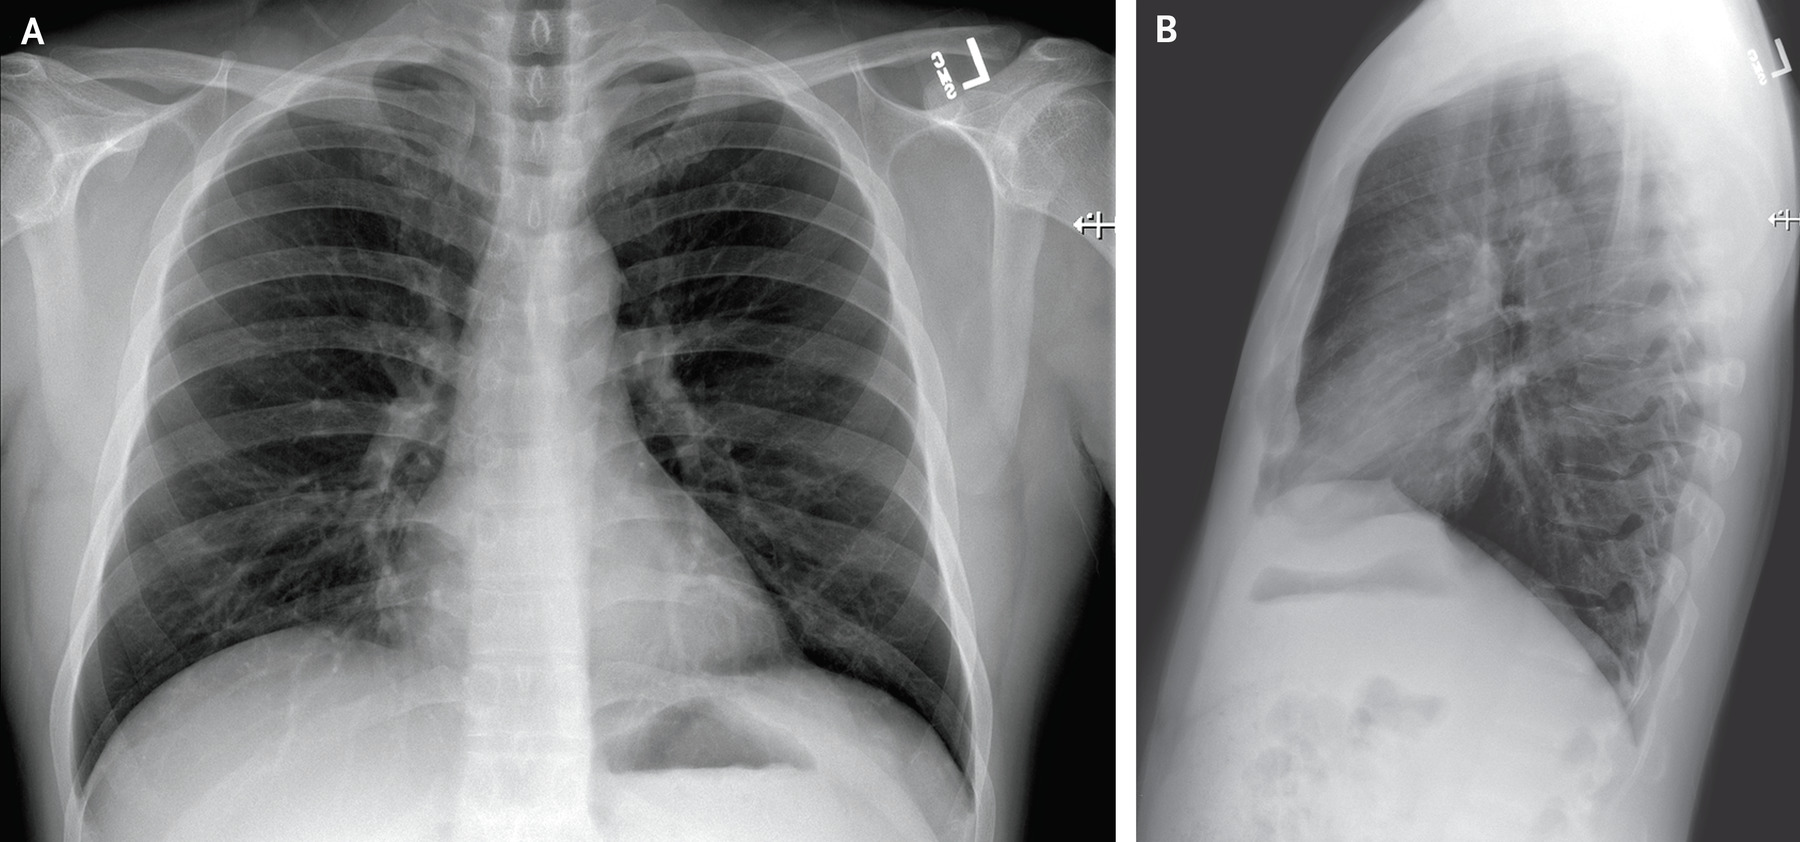

经过医生的详细检查,小杰被确诊为肺炎,这个消息对于他和他的家人来说无疑是一个巨大的打击,小杰是个乐观的年轻人,他决定勇敢地面对这场“肺部冒险”。